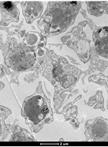

Plasmodium sporozoites are the infectious, highly motile forms of the malaria parasite transmitted by Anopheles mosquitoes. Sporozoite motility can be assessed following the dissection of Anopheles salivary glands and isolation of sporozoites in vitro.